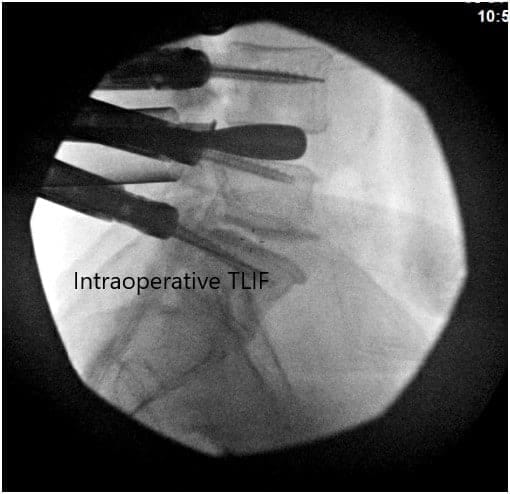

Based on fluoroscopic imaging, we felt that a size #12 implants would be satisfactory and therefore we proceeded to obtain a crescent PEEK cage measuring 30 x 12 mm and packed it with demineralized bone matrix as well as BMP. We then proceeded to place the cage into position. The edge of the inferior L4 vertebral body was removed using an osteotome in order to allow for the entry of the implant.

Once we are satisfied with the positioning of the implant, we then evaluated its position on the both AP and lateral planes and proceeded to place bone graft posteriorly behind the implants within the intervertebral body. We then washed up the area with normal saline and reevaluated the nerve root and dura.

There were no signs of compression and we are really satisfied with the positioning and alignment of the interbody fusion implants and bone graft. We then turned our attention towards the L5-S1 region. Similarly, we used a size #15 blade to create an annulotomy and then proceeded to place several curettes in order to perform a microdiscectomy and prepare the intervertebral space for an implant.

Intraoperative Fluoroscopic Images.